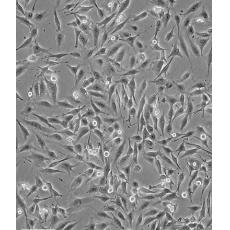

中文名稱 人乳腺癌高轉(zhuǎn)移細胞

生長特性 loosely adherent with floating clusters

形態(tài)特征 epithelial

細胞描述 該細胞1976年建系,源自一位48歲患有乳腺癌女性的胸腔積液,但近來有研究證明該細胞被M14黑色素瘤細胞污染。